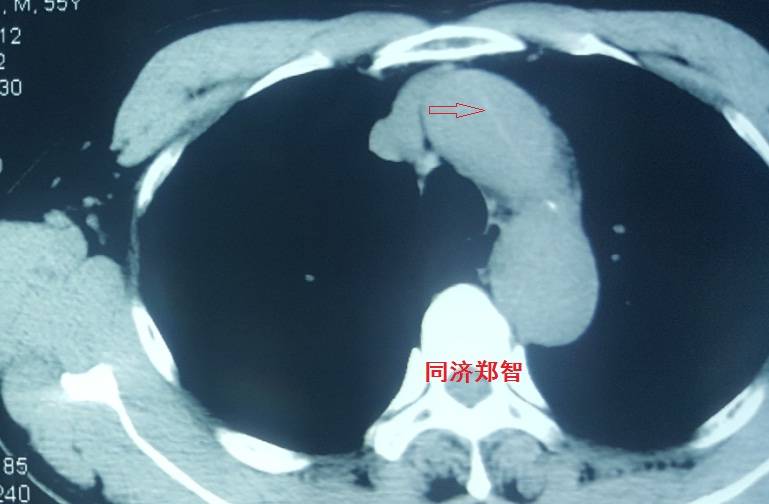

病例三

胸部平扫CT提示胸降动脉增宽(红色星形标记),CTA证实B型主动脉夹层伴降主动脉夹层动脉瘤形成。